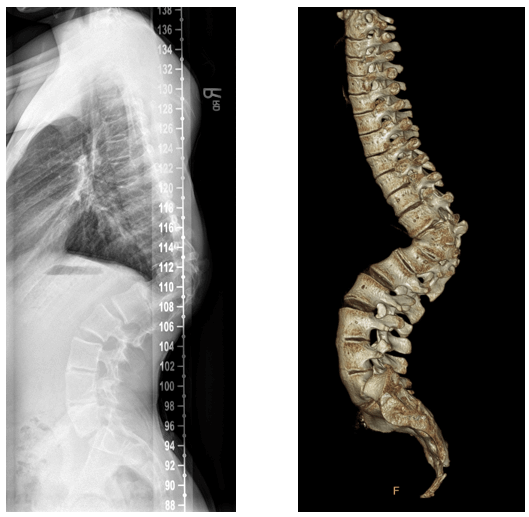

Pre-surgery radiographs including 3D CT reconstruction showing the congenital vertebral abnormality causing acute kyphosis.